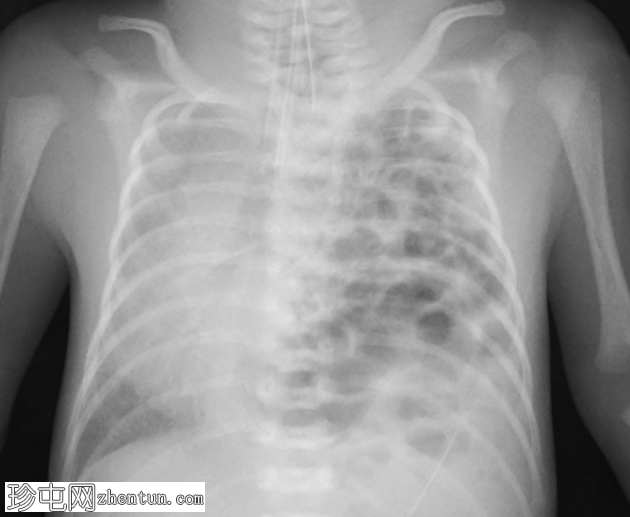

正位片

左侧胸腔可见囊性透亮区,膈下肠袢稀少。左未显影,可能发育不良。纵隔向右侧移位。脐静脉导管指向左侧,其尖端位于膈肌上方。

气管插管位置良好。

胃管尖端位于上纵隔的囊袋内。

右肺容积较小。

左侧先天性膈疝的特征,伴有食管闭锁和气管食管瘘。